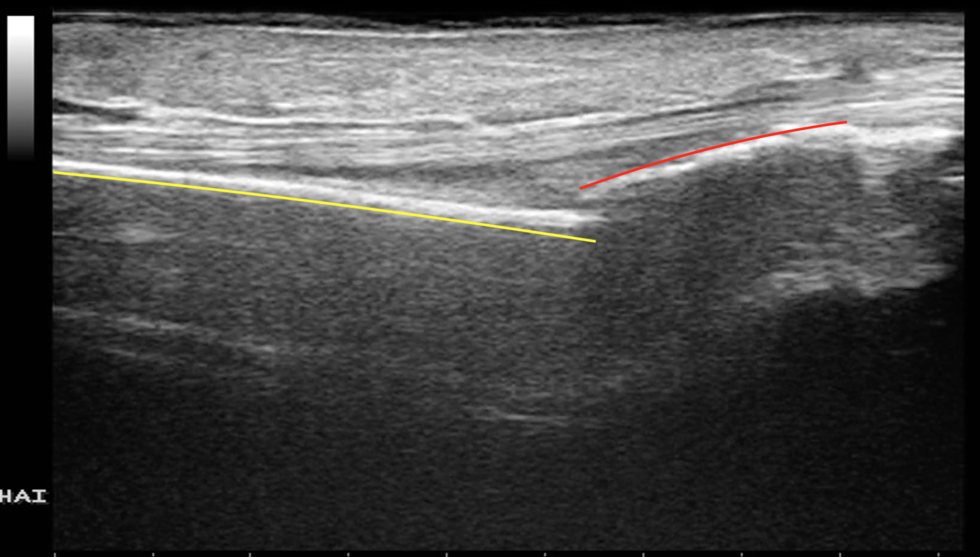

整復前

黄色線:近位骨片

赤色線:遠位骨片

触診により確認していくと、橈骨遠位部が変形し骨折していることが強く疑われました。

念のためエコーでも確認してみると、橈骨遠位端部が骨折し、転位(骨がずれて変形)していることが確認できました。

転位をそのままにしておくと後遺症が残りやすいため、患者さんにご説明し整復操作を行うことといたしました。